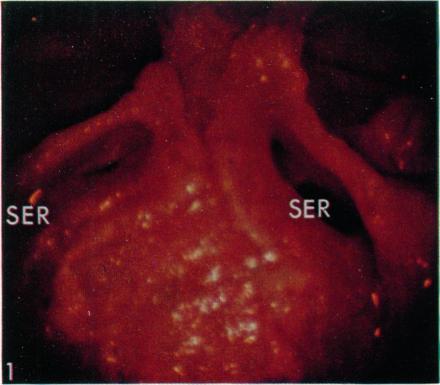

Surgical aspects of the anatomy of the sphenoidal sinuses and the sella turcica.

J Anat. 1977 Dec;124(Pt 3):541-53.